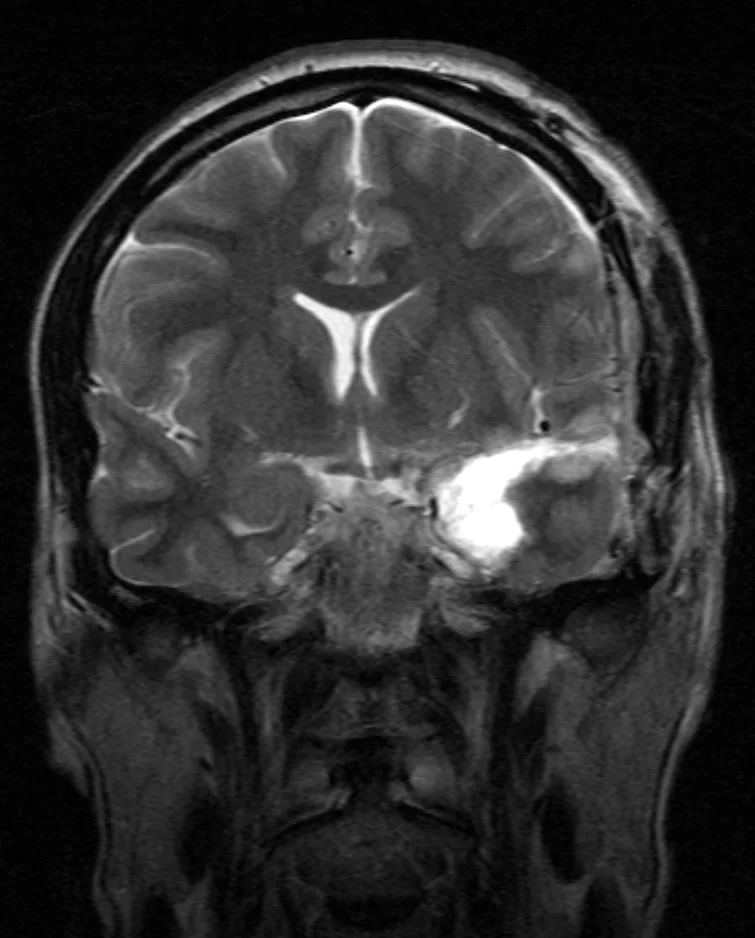

Ο απεικονιστικός έλεγχος με μαγνητική τομογραφία ανέδειξε πάχυνση του αριστερού ιπποκάμπου και της αμυγδαλής με μικροφυσαλλιδώδη στοιχεία. Στη διαφορική διάγνωση ετέθη το χαμηλόβαθμο γλοίωμα, το DNET και η σκλήρυνση του ιπποκάμπου.

Η μετεγχειρητική μαγνητική τομογραφία εγκεφάλου δείχνει την πλήρη εξαίρεση της βλάβης με διατήρηση του νεοφλοιού. Η ιστολογική εξέταση ανέδειξε γαγγλιογλοίωμα WHO I καθώς επίσης και στοιχεία σκλήρυνσης του ιπποκάμπου.